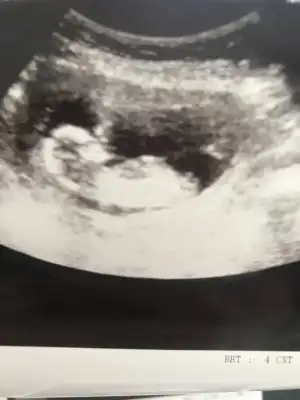

dr soylemeden siz gorun genital nub teorisi ( bebegin cinsiyeti)

Banada cinsiyet tahmini yapar mısınız

• IMG_20210430_093326.webp

IMG_20210430_093326.webp

28,9 KB · Görüntüleme: 77